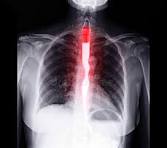

Síndrome de Boerhaave

El Síndrome de Boerhaave o rotura esofágica, es el resultado de un repentino aumento de la presión interna del esófago producida durante los vómitos intensos, a consecuencia de una incoordinación neuromusucular que causa un fallo del cierre del músculo cricofaríngeo (el esfínter superior del esófago).

Diagnóstico del Síndrome de Boerhaave